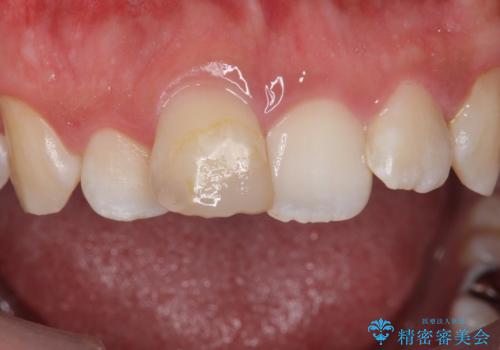

- 前歯の変色を主訴に来院。

神経が死んでいたため、神経の治療を行いました。

神経が死んでしまった歯は時間がたつと変色してきてしまいます、セラミックでかぶせると色を改善することが可能です。